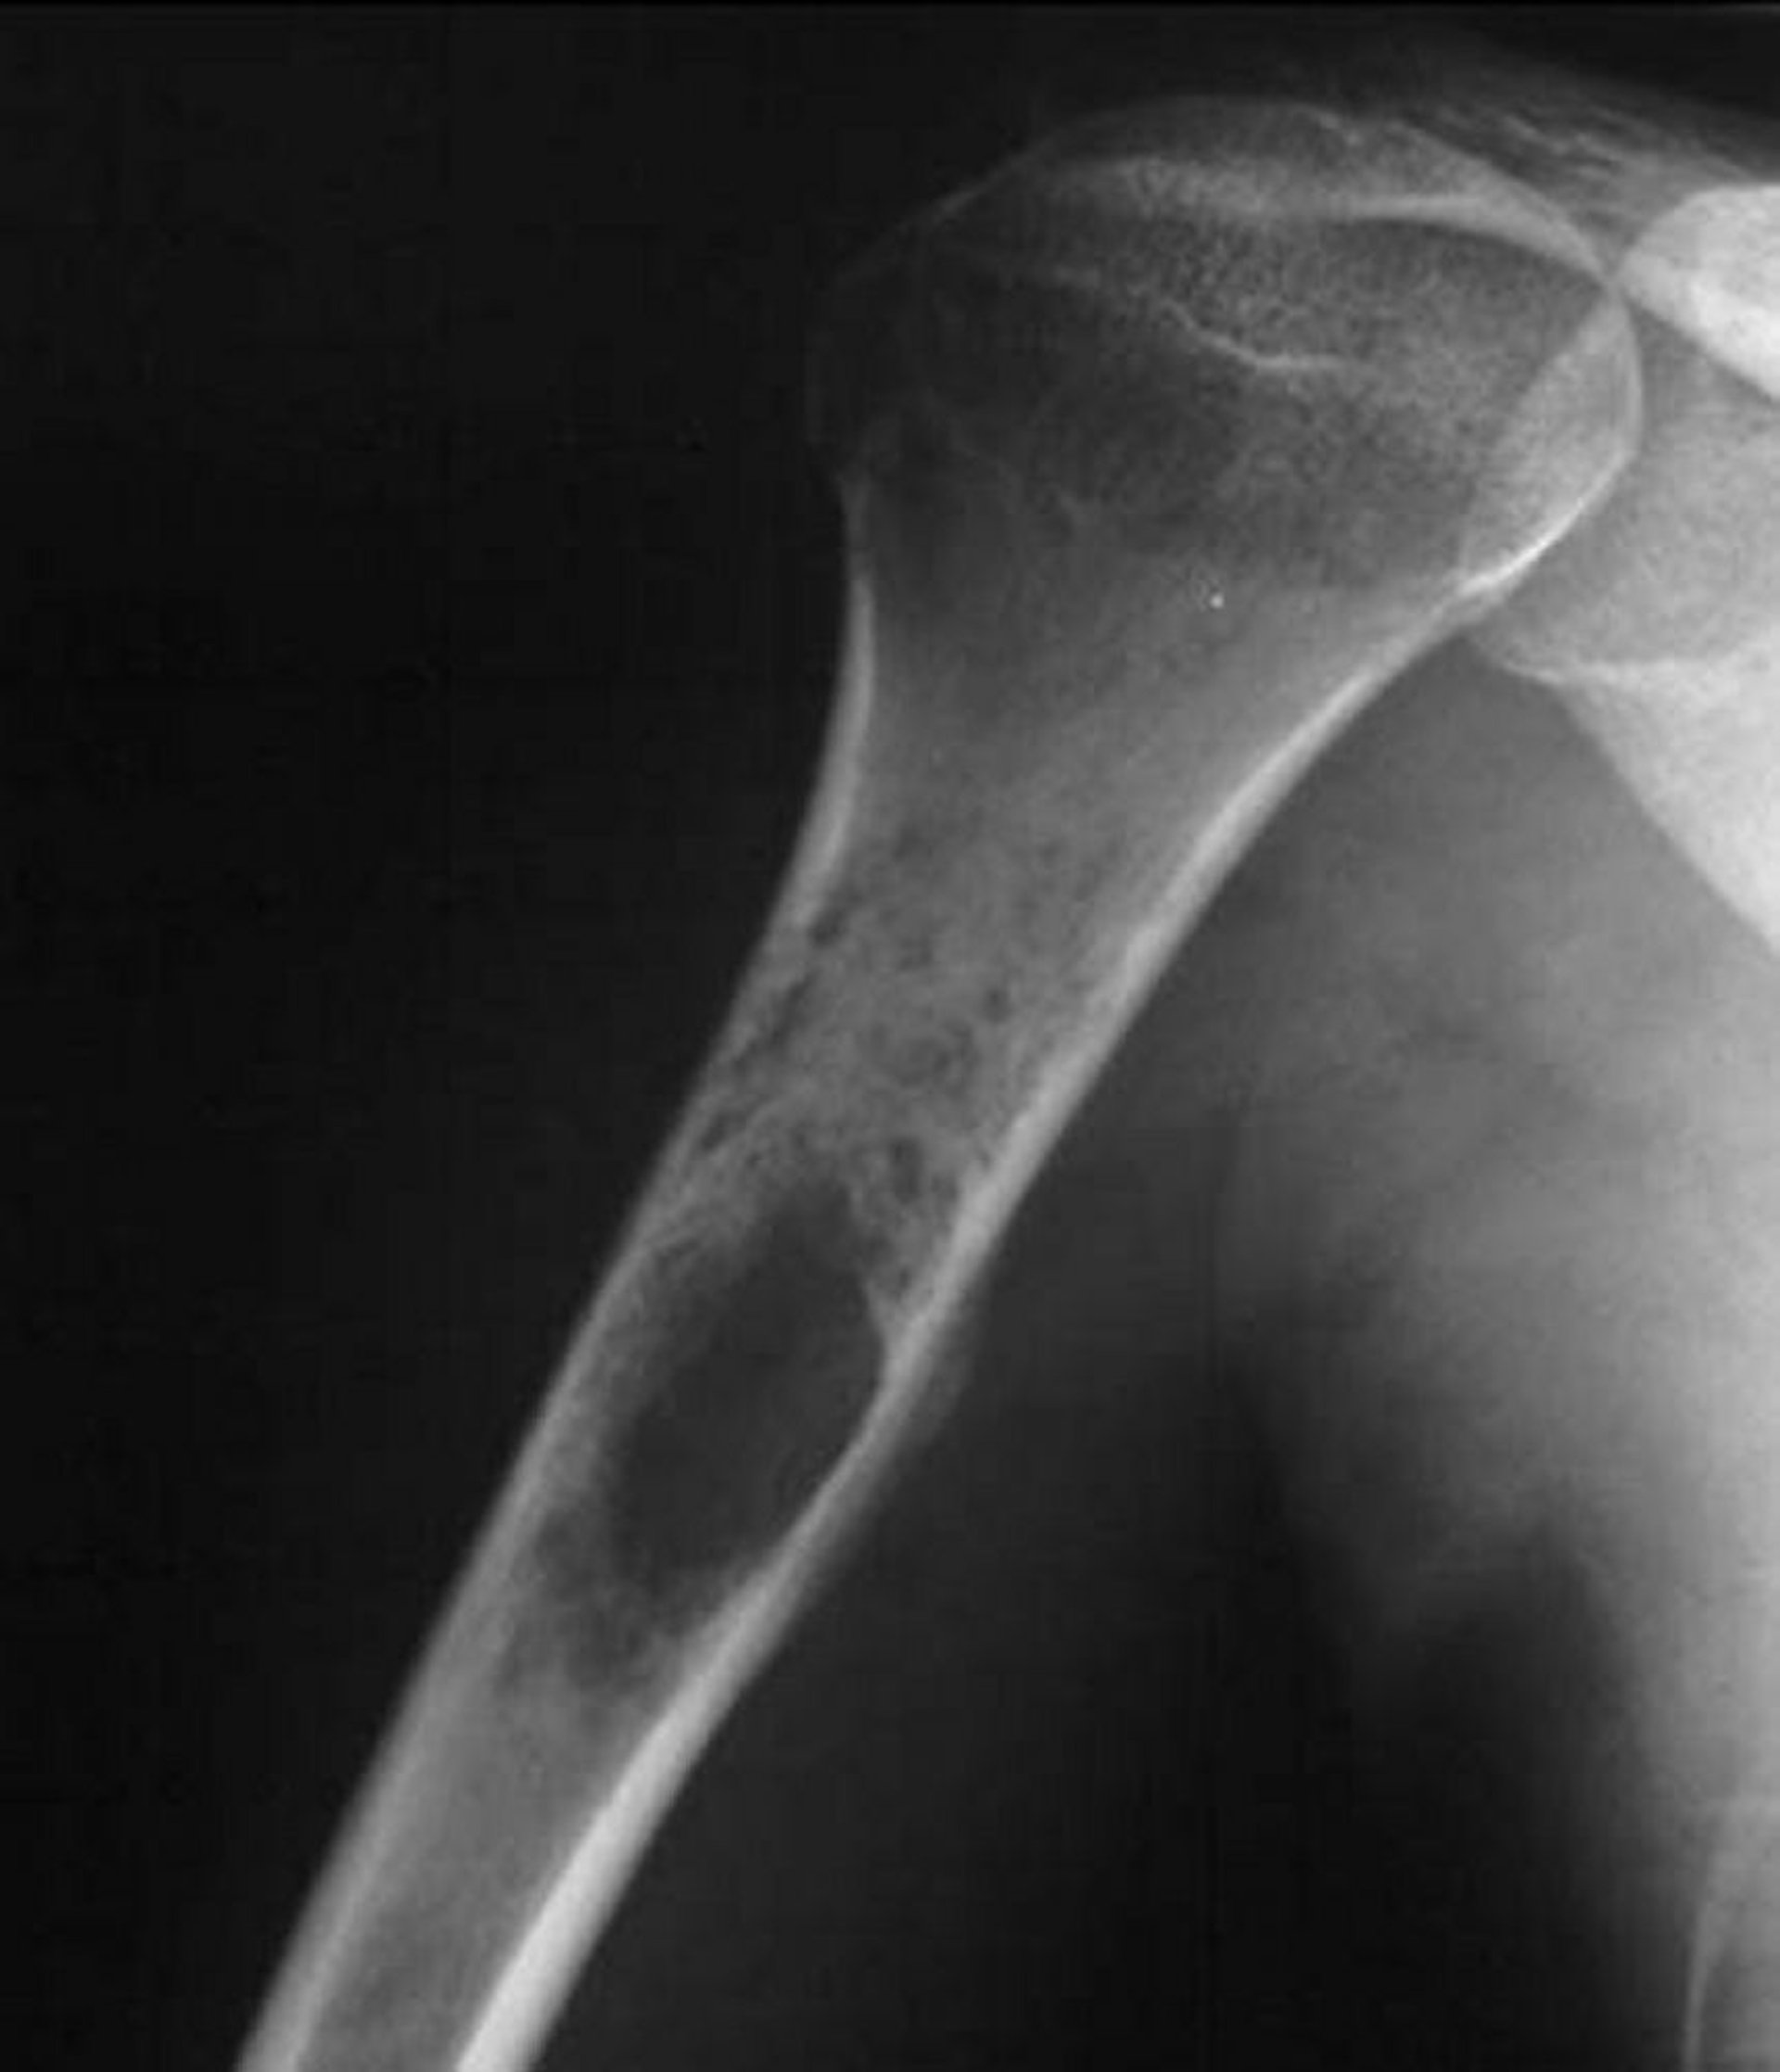

この肩関節X線写真には,ユーイング肉腫に典型的な上腕骨内の破壊性の腫瘍がみられる。

Image courtesy of Michael J.Joyce, MD, and Hakan Ilaslan, MD.